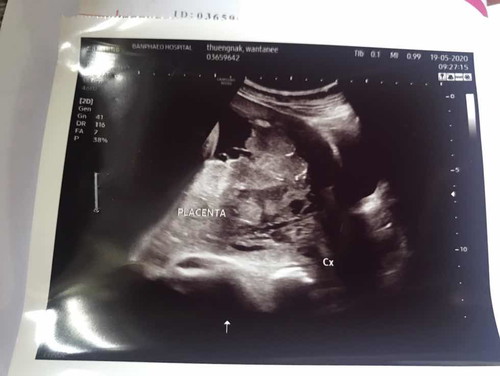

รกเกาะต่ำ ต้องผ่าคลอด 37 สัปดาห์

หมอนัดผ่าคลอด 4 มิย แล้วค่ะ เนื่องจากรกเกาะต่ำ ปิดปากมดลูกทั้งหมด น้อง 37 สัปดาห์ หมอรอครบกำหนดไม่ได้ เสี่ยงแม่ตกเลือด อาทิตย์หน้าหมอให้คุณสามีไปคุยเรื่องความเสี่ยงในการผ่าคลอด อีกอาทิตย์พร้อมผ่า กลัวมากค่ะ